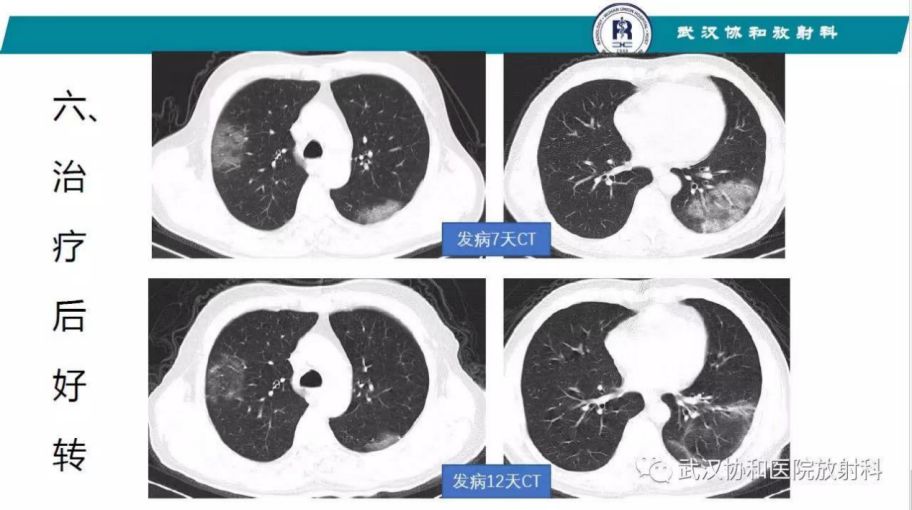

如果病人的呼吸道症状和CT影像符合冠状病毒肺炎(参考武汉协和医院放射科提供的影像诊断标准),在没有检测试剂确诊的情况下,也应当及时隔离,及时治疗。在有阳性接触史和旅行史的情况下,可以做出2019-nCoV 肺炎的临床诊断并采取相应措施。

根据现有临床资料(Lancet Jan 2020; NEJM Jan. 2020; Lancet Feb. 2020), 大部分新型冠状病毒的临床表现有相对典型的发热及下呼吸道症状,和CT 早期多发性磨玻璃病变和后期肺实变(详细请见武汉协和医院放射科的建议和和标准。他们在一线,最有发言权);

附CT 诊断要点(详见武汉协和医院放射科建议)

早期病变为局部斑片状亚段分布为主

进展期多个累及多个肺叶,并出现部分实变

重症期双肺弥散性实变”白肺” 。

鉴别诊断包括其他病毒或者细菌感染引起的肺炎。

附协和医院放射科的诊断标准图: